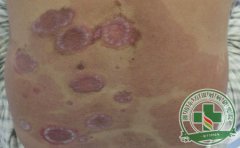

银屑病治疗不当可能造成的严重后果

银屑病治疗难度本就不小,相信众多患者都深有感触。如果在此基础上,患者选择的银屑病治疗方法不对,或者治疗不及时,亦或者各种治疗不当的问题出现,都有可能带来不容忽视的 [详细]